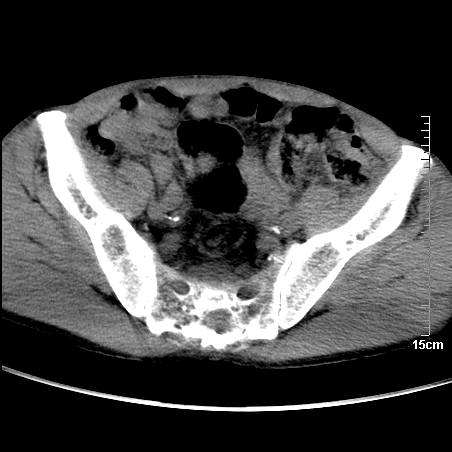

标题: CT16886:骶尾部占位:1.脊索瘤?2.巨细胞瘤?

增强:

1、骶尾部巨大软组织肿块,部分骶尾骨以被软组织肿块代替,呈不规则侵蚀;病变突向盆腔内;增强扫描病变呈不均质强化;首先考虑脊索瘤。不支持的一点就是病变内无钙化。

2、发生于骶尾椎者须与骨巨细胞瘤鉴别,骨巨细胞瘤一般发在上疗骶椎,肿瘤内无钙化,一般无侵袭性生长的表现。